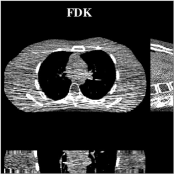

Fig.Β 5 shows the reconstructions and the corresponding error (magnitudes) images (shown for the central axial, sagittal, and coronal planes) for FDK, PWLS-EP, and PWLS-ULTRA () with the patch-based weights. Compared to FDK and PWLS-EP, PWLS-ULTRA significantly improves image quality by reducing noise and preserving structural details (see zoom-ins). Fig.Β 6 shows the RMSE for each axial slice in the PWLS-EP and PWLS-ULTRA (with the weights ) reconstructions. PWLS-ULTRA clearly provides large improvements in RMSE for many slices, with greater improvements near the central slice.

Fig.Β 7 shows the reconstructions (shown for the central axial plane in the 3D volume) for FDK (provided by GE Healthcare), PWLS-EP (corresponds to Fig.Β 8(a)), and PWLS-ULTRA with (corresponds to Fig.Β 9(a)). The PWLS-ULTRA reconstruction has lower artifacts and noise. Moreover, the image features and edges are better reconstructed by PWLS-ULTRA than by PWLS-EP or FDK.